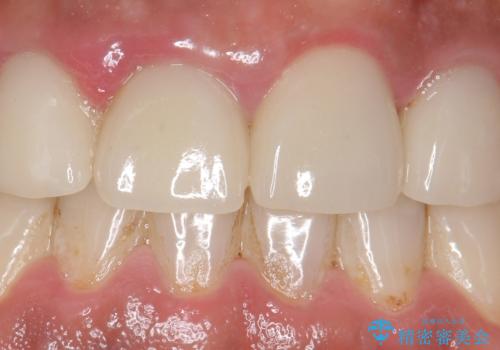

- 右上の前歯が土台ごと外れたといらっしゃった方の症例です。

ファイバーコアという土台から建て直し、咬み合わせに十分注意した上で、オールセラミッククラウンによる補綴を行いました

今回用いたオールセラミッククラウンはジルコニアフレームという白い素材の上にセラミックを盛っているため、審美性が非常に高いのが特徴です。

また、ジルコニアは人工ダイヤモンドの材料にも使われているほど高い強度を持っており、そのためオールセラミッククラウンは審美性だけでなく、奥歯やブリッジの補綴も可能とするクラウンです。